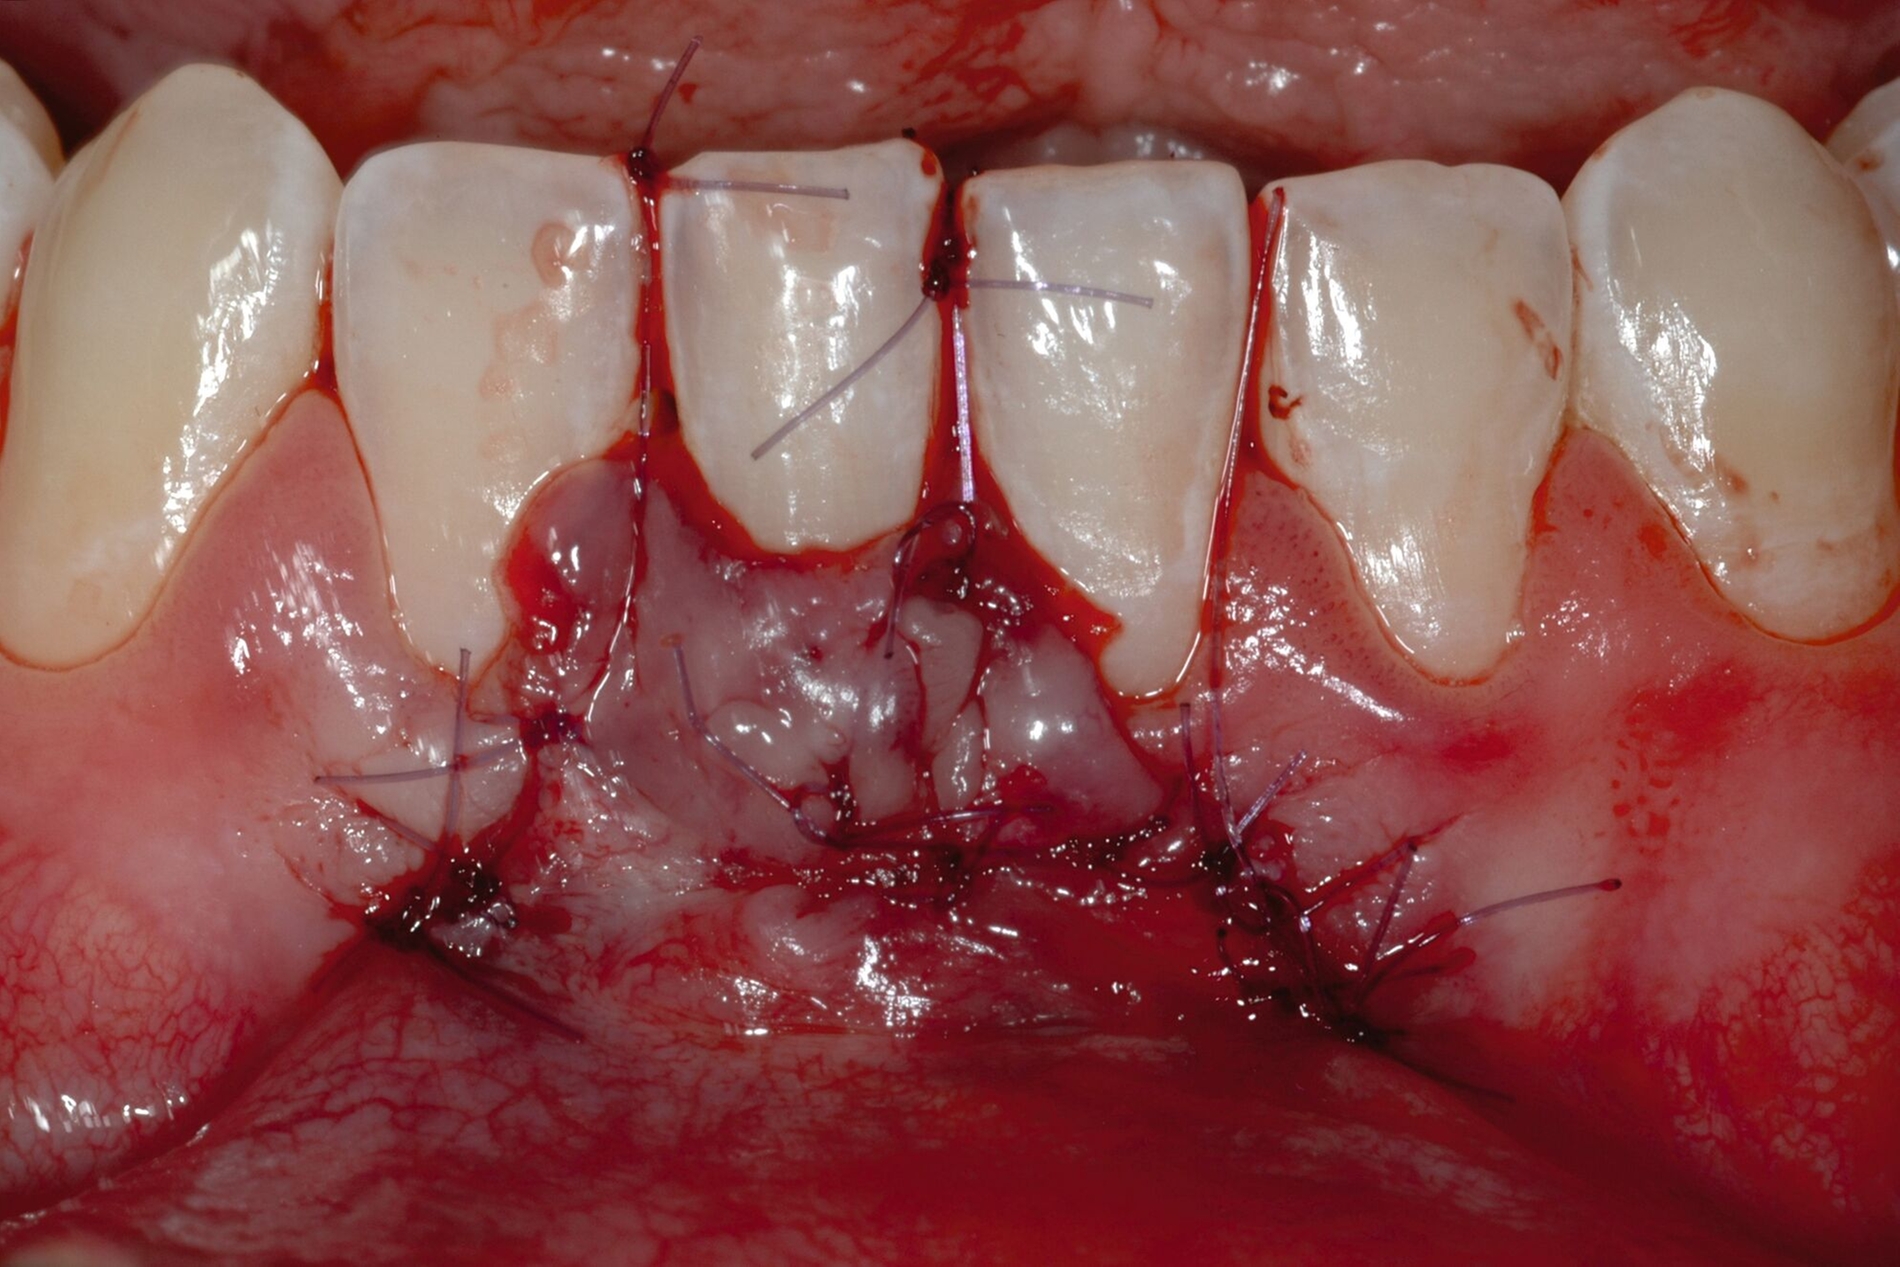

Tunkel et al. versuchten die Vorteile von Zucchellis Koronalem Verschiebelappen und Sculeans Lateral Geschlossenem Tunnel in einer Technik zu vereinen: dem Lateral Geschlossenen Koronalen Verschiebelappen (LCAF) [Tunkel et al., 2024] (Abbildung 3). Bei dieser Methode, mit der vor allem tiefe singuläre parodontale Rezessionen behandelt werden, wird die Koronalverschiebung ohne Entlastungsinzisionen kombiniert mit dem lateralen Verschluss der tiefen parodontalen Rezession.

Das Vorgehen ist hier wie folgt: Zunächst wird im Bereich der tiefen Rezession der Gingivarand geringfügig exzidiert, um ein Zusammenwachsen der geschlossenen Lappenanteile zu ermöglichen. Anschließend wird der Schnitt in horizontaler Richtung durch leicht bogenförmige Schnittführungen auf Höhe der Schmelz-Zement-Grenze erweitert, um mindestens zwei Zähne rechts und links von der Rezession (Abbildung 3b). Im Unterkiefer-Frontzahnbereich, wo die Rezessionen heutzutage am häufigsten vorkommen, sollte der Lappen mindestens von Eckzahn zu Eckzahn gebildet werden, um ein harmonisches Ergebnis nach Abheilung zu erreichen. Auf vertikale Entlastungsinzisionen kann komplett verzichtet werden. Anschließend erfolgt die Lappenpräparation nach dem bereits für koronale Verschiebelappen gängigen Prinzip teilschichtig-vollschichtig-teilschichtig.

Die Papillenbereiche werden mit dem Skalpell scharf vom Periost abgelöst. Dann wird das Periost durchtrennt und bis zur mukogingivalen Grenze ein vollschichtiger Lappen gebildet. Nach Überschreiten dieser wird wieder zweischichtig präpariert. Hierdurch wird eine gute Mobilisation des Lappens erreicht, die eine ausreichende Koronalverschiebung ermöglicht. Entgegen dem in früheren Jahren propagierten komplett teilschichtigen Vorgehen, kann durch dieses Verfahren die Gefahr von Lappenperforationen signifikant gesenkt werden, da diese insbesondere im Bereich der mukogingivalen Grenze auftreten. Nachdem die Lappenareale mesial und distal der Rezession gelöst sind, können diese durch zwei bis drei feine monofile Nähte miteinander verbunden werden (Abbildung 3c). Sobald durch diese Naht ein zusammenhängender koronaler Verschiebelappen entstanden ist, werden die Papillenbereiche koronal des gebildeten Lappens entepithelialisiert. Nach Entnahme eines Bindegewebstransplantats oder entepithelialisierten freien Schleimhauttransplantats wird die Wurzeloberfläche mit EDTA-Gel konditioniert und anschließend werden Schmelz-Matrix-Proteine aufgetragen (Abbildung 3d). Diese bewirken die Bildung eines new attachment und fördern zudem die Wundheilung, was gerade bei den delikaten lateralen Verschiebelappen von Vorteil sein sollte [McGuire und Cochran, 2003; Almqvist et al., 2011; Thoma et al., 2011; McGuire et al., 2016]. Anschließend wird das Transplantat durch Nähte ausgehend vom oralen Papillenbereich fixiert (Abbildung 3e). Zuletzt wird der Lappen mit sogenannten doppelten Umschlingungsnähten im Bereich der Papille durch Zug nach koronal und oral fixiert, was eine perfekte Positionierung ermöglicht [Zuhr et al., 2009] (Abbildung 3f). Hierbei muss darauf geachtet werden, dass der Lappen die Schmelz-Zement-Grenze um mindestens 2 mm überdeckt, um eine hundertprozentige Wurzeldeckung erwartbar zu machen [Pini Prato et al., 2005].

Der Lateral Geschlossene Koronal Verschobene Lappen ermöglicht eine annähernd narbenfreie Deckung singulärer parodontaler Rezessionen durch Verzicht auf vertikale Entlastungsinzisionen (Abbildung 3g). Das Lösen der Papillen im Rahmen der Verschiebung ermöglicht eine deutliche Anhebung des Lappens und somit durch großzügige Überdeckung das Erreichen vollständiger Wurzeldeckungen. Durch den lateralen Verschluss im Rahmen der tiefen, über die mukogingivale Grenze hinausgehenden Rezession kann keratinisierte Gingiva im Bereich dieser hergestellt und eine übermäßige Mobilisation und damit Einschränkung des Vestibulums verhindert werden.